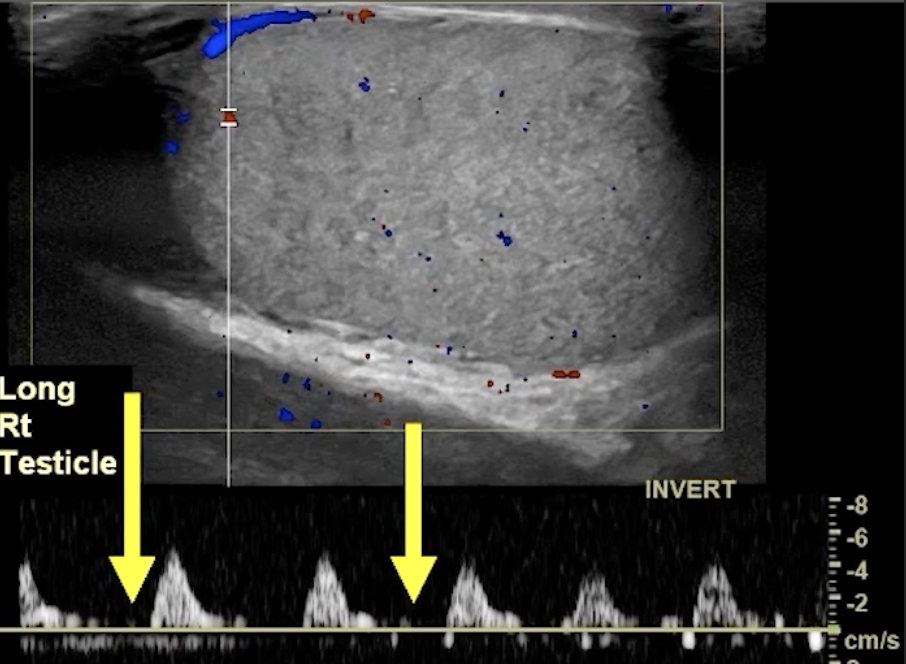

• Partial Torsion

• May have some blood flow

• Decreased or reversal of flow in diastole (no line in between peaks) - indicates high resistance state (top images)

• Blunted arterial peak (not as sharp as a point in systole) ( bottom images)